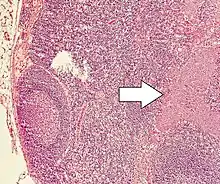

Lymph node metastasis of a neuroendocrine tumor.

Currently there is no one staging system for all neuroendocrine neoplasms. Well-differentiated lesions generally have their own staging system based on anatomical location, whereas poorly differentiated and mixed lesions are staged as carcinomas of that location. For example, gastric NEC and mixed adenoneuroendocrine cancers are staged as primary carcinoma of the stomach.[38]